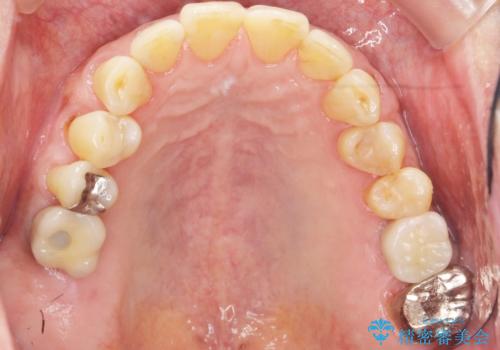

奥歯のインプラント ソケットリフト 60代男性

- 奥歯のインプラントをご希望し、来院された患者様です。

精査したところ上顎骨の厚みが薄かったため、ソケットリフト(上顎洞底挙上術)を併用してインプラント治療を行いました。

審美的・機能的な仕上がりに喜んで下さいました。

また、半年という比較的短期間でインプラント治療が終わったことにもご満足頂けました。